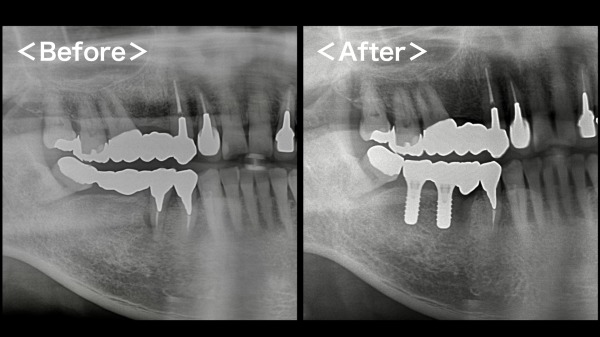

初診時のレントゲン写真がこちらになります。

右下にブリッジが入っており、その支えとなっている右下5番目の周囲の歯茎に腫れを認めておりました。

こちらが術後のレントゲン写真になります。